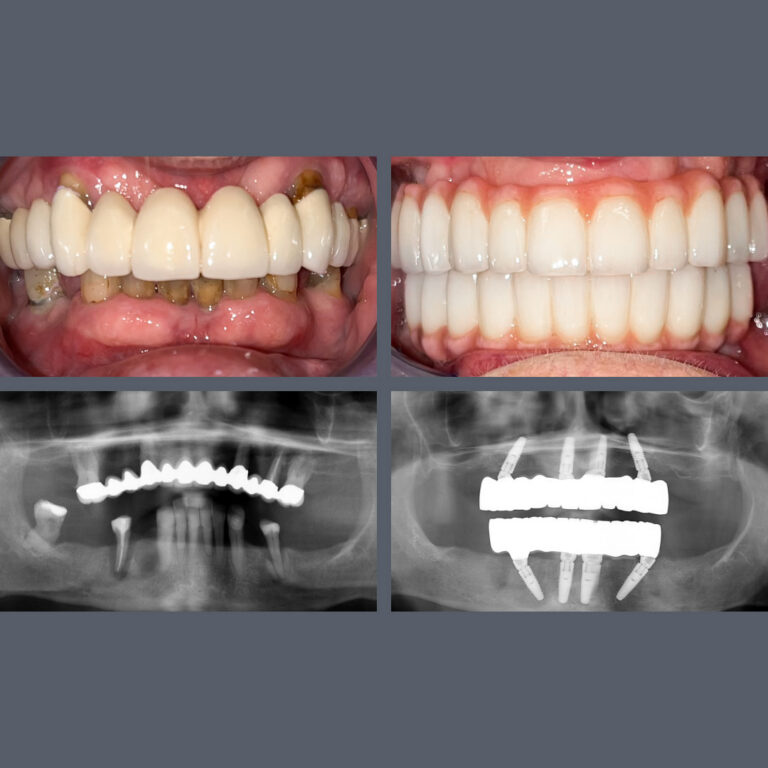

Tandimplantatproducenten Nobel Biocare har tildelt Madenta prisen “All-on-4® Center of Excellence”. Prisen gives til klinikken for det højeste antal All-on-4® behandlinger i Budapest og for enestående faglighed på højeste niveau.

Med denne anerkendelse regnes vores tandlæger blandt de førende specialister i Ungarn inden for All-on-4® behandlinger. Vi går ikke på kompromis og anvender udelukkende højkvalitets Nobel-implantater i vores All-on-4® behandlinger.

Specialiseret behandling giver smukke smil

Mange af vores udenlandske patienter kommer til os for implantater, kirurgiske indgreb og protetiske behandlinger, med håb om at kunne rejse hjem efter få dage med et både funktionelt og æstetisk smukt smil. Du er kommet til det rette sted! Vores specialister er internationalt anerkendte, og når de arbejder sammen på tværs af specialer, er næsten intet umuligt.